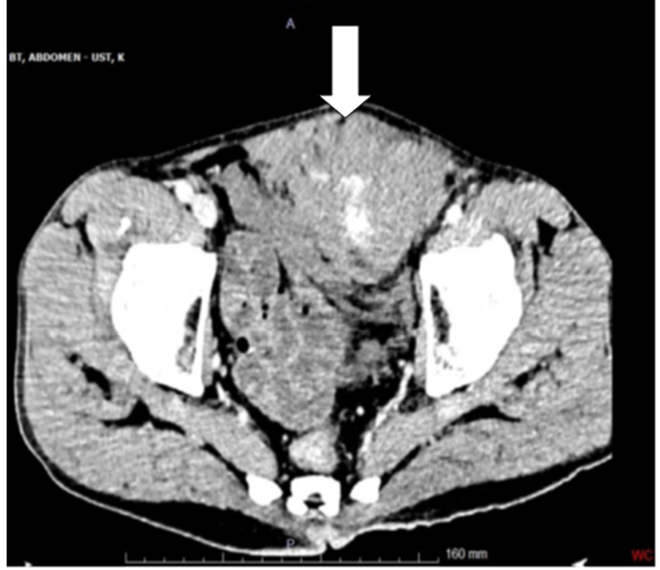

Intraoperative findings showed intact small intestine, colon, spleen, and other abdominal organs. A large hematoma in the left rectus muscle extended into the peritoneal cavity. Hemostasis was achieved by suturing the bleeding vessels within the rectus muscle. A Jackson-Pratt (JP) drain was placed between the muscle planes, and a silicone drain was positioned in the pelvic region. During surgery, the patient received two units of erythrocyte suspension and one unit of fresh frozen plasma and was transferred to the intensive care unit (ICU) for postoperative monitoring. During the surgery, the foreign body was removed from the sheath hematoma. Postoperatively, hemoglobin dropped to 7.6 g/dL, and hematocrit fell to 22.2%. While the JP drain remained inactive, the pelvic silicone drain collected 500 cc of hemorrhagic fluid. Despite this, the patient remained stable and received further transfusions. A follow-up CT on postoperative day 3 showed regression of the hematoma (Figure 3), The patient gradually improved and remained hemodynamically stable throughout the ICU stay.

Figure 3: Resolution in Left Rectus sheath hematoma after surgery

This case underscores the need for a high suspicion of RSH in patients with abdominal pain and a trauma history, especially with anticoagulation or other risk factors. Timely imaging and intervention can avert severe complications like intraperitoneal bleeding. It also highlights the importance of careful monitoring in stable patients, as sudden clinical deterioration can occur. The patient was monitored in the ICU, and on postoperative day 3, a follow-up CT scan showed regression of the rectus muscle hematoma(Figure 3), though it had not fully resolved. Throughout the ICU stay, the patient remained hemodynamically stable and showed gradual improvement. This case intersects with other specialties like radiology, hematology, or critical care, and underscores the need for high suspicion of RSH in trauma cases, timely intervention to prevent complications, and vigilant monitoring during recovery. The need for protocols to diagnose and manage atypical RSH presentations and further investigation are recommended. When deciding between surgery and conservative treatment for rectus sheath hematoma (RSH), patient stability and the extent of bleeding are key factors: